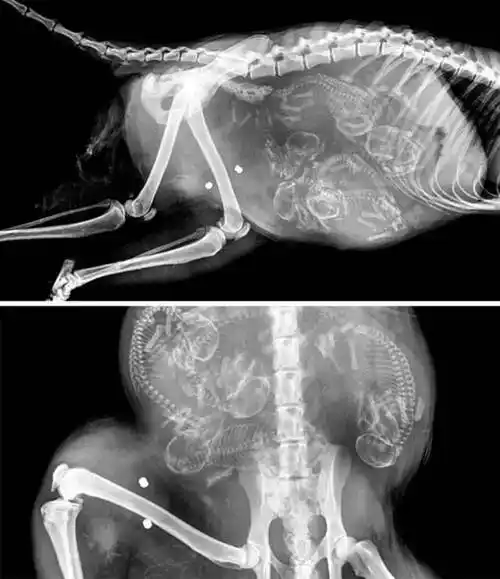

是惊悚还是萌?动物怀孕x光照